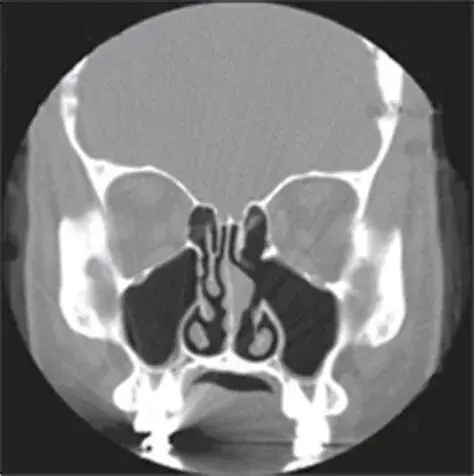

空鼻症的临床标志是“矛盾的鼻塞”,也就是从影像学和解剖上看,因缺乏下鼻甲而导致鼻的呼吸腔道宽大而明显,但是患者依然主诉“鼻子不通气”,或者有类似的难以言状的感觉,如感觉不到气流、气短、呼吸困难,甚至要求辅助通气设备来解决“气促”问题。

正常的鼻腔,有上、中、下三个鼻甲,其中下鼻甲参与构成了鼻腔中最狭窄和柔软的通道组成。

萎缩性鼻炎的临床表现与空鼻症最为相似,都有鼻腔异常宽大、鼻甲明显缩小、干燥、大量结痂、异味甚至恶臭等症状和体征。